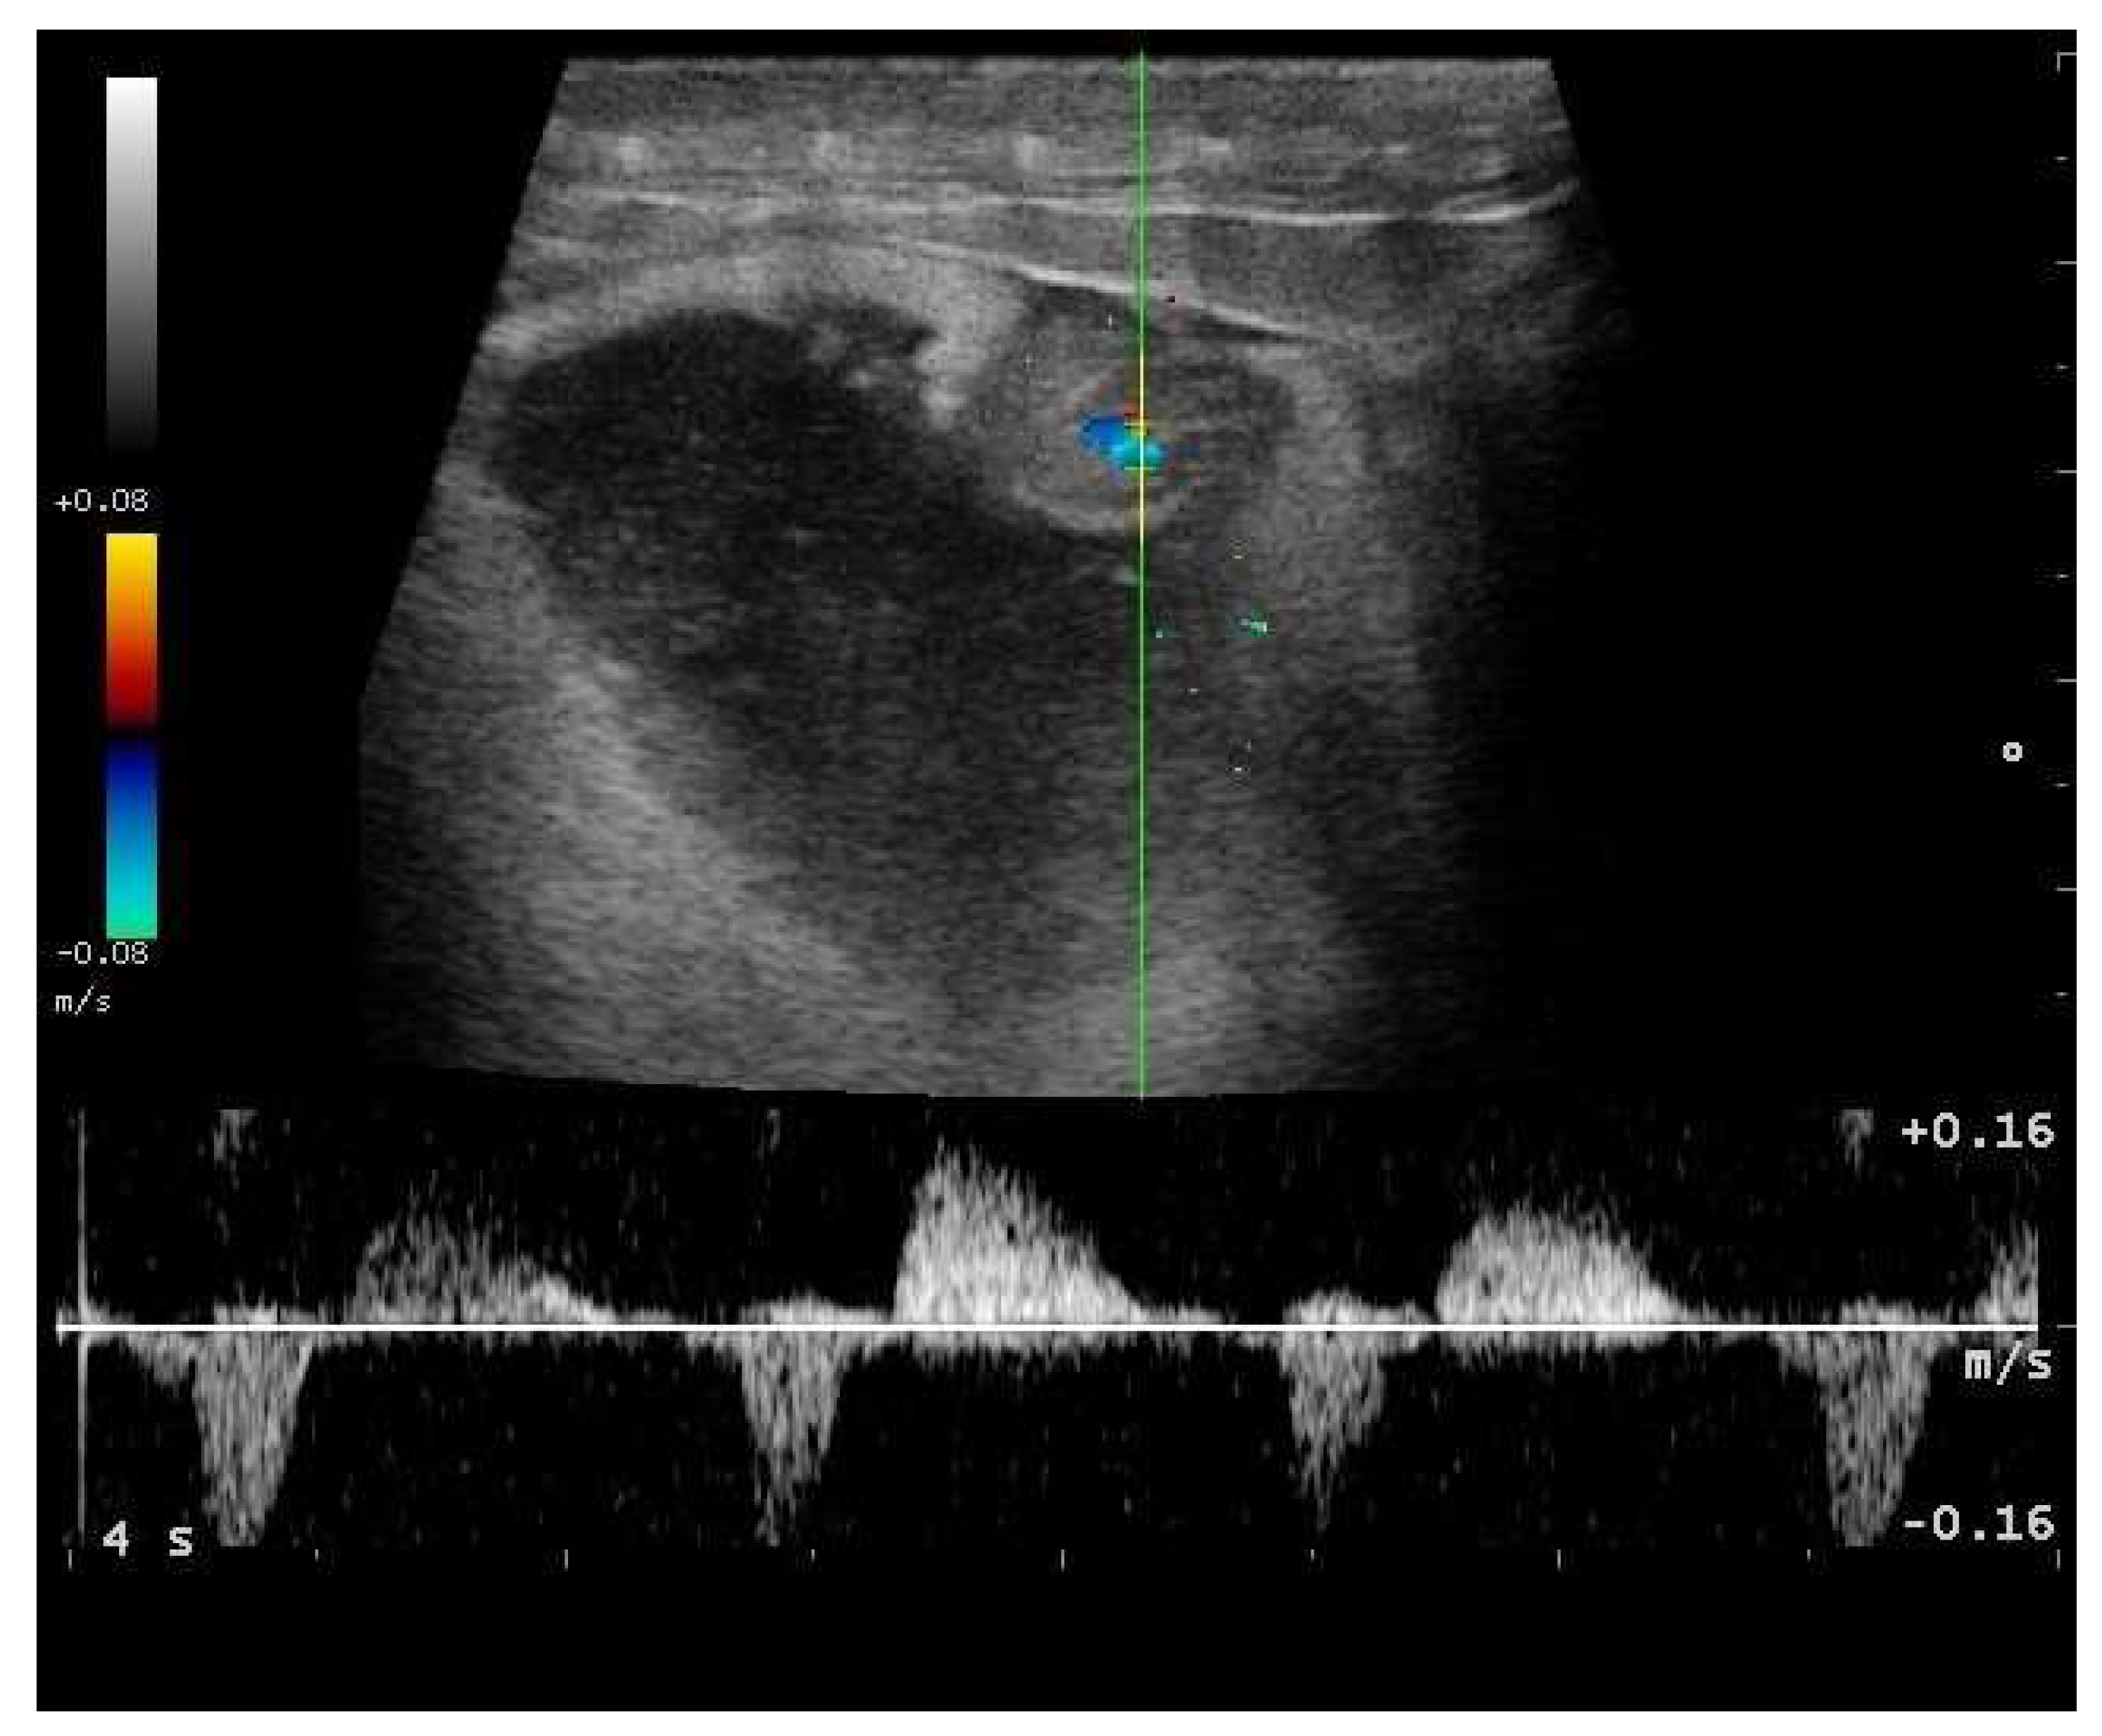

- Garcia, V.C.; Almeida-Santos, S.M. Reproductive cycles of neotropical boid snakes evaluated by ultrasound. Zoo Biol. 2021, 1–10. [Google Scholar] [CrossRef]

- Isaza, R.; Ackerman, N.; Jacobson, E.R. Ultrasound imaging of the coelomic structures in the Boa constrictor (Boa constrictor). Vet. Radiol. Ultrasound 1993, 34, 445–450. [Google Scholar] [CrossRef]

- Bigliardi, E.; Denti, L.; De Cesaris, V.; Bertocchi, M.; Di Ianni, F.; Parmigiani, E.; Bresciani, C.; Cantoni, A.M. Colour Doppler ultrasound imaging of blood flows variations in neoplastic and non-neoplastic testicular lesions in dogs. Reprod. Domest. Anim. 2019, 54, 63–71. [Google Scholar] [CrossRef]